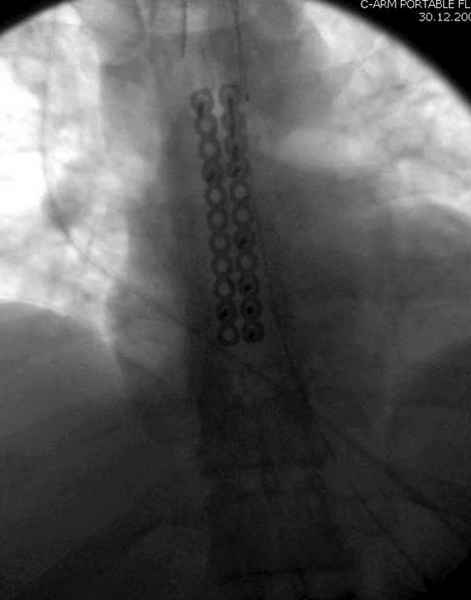

А простые посттравматические ложные суставы грудины приходилось оперировать с ограничителем сверла и с фиксацией 2.4 мм пластинами с угловой стабильностью.